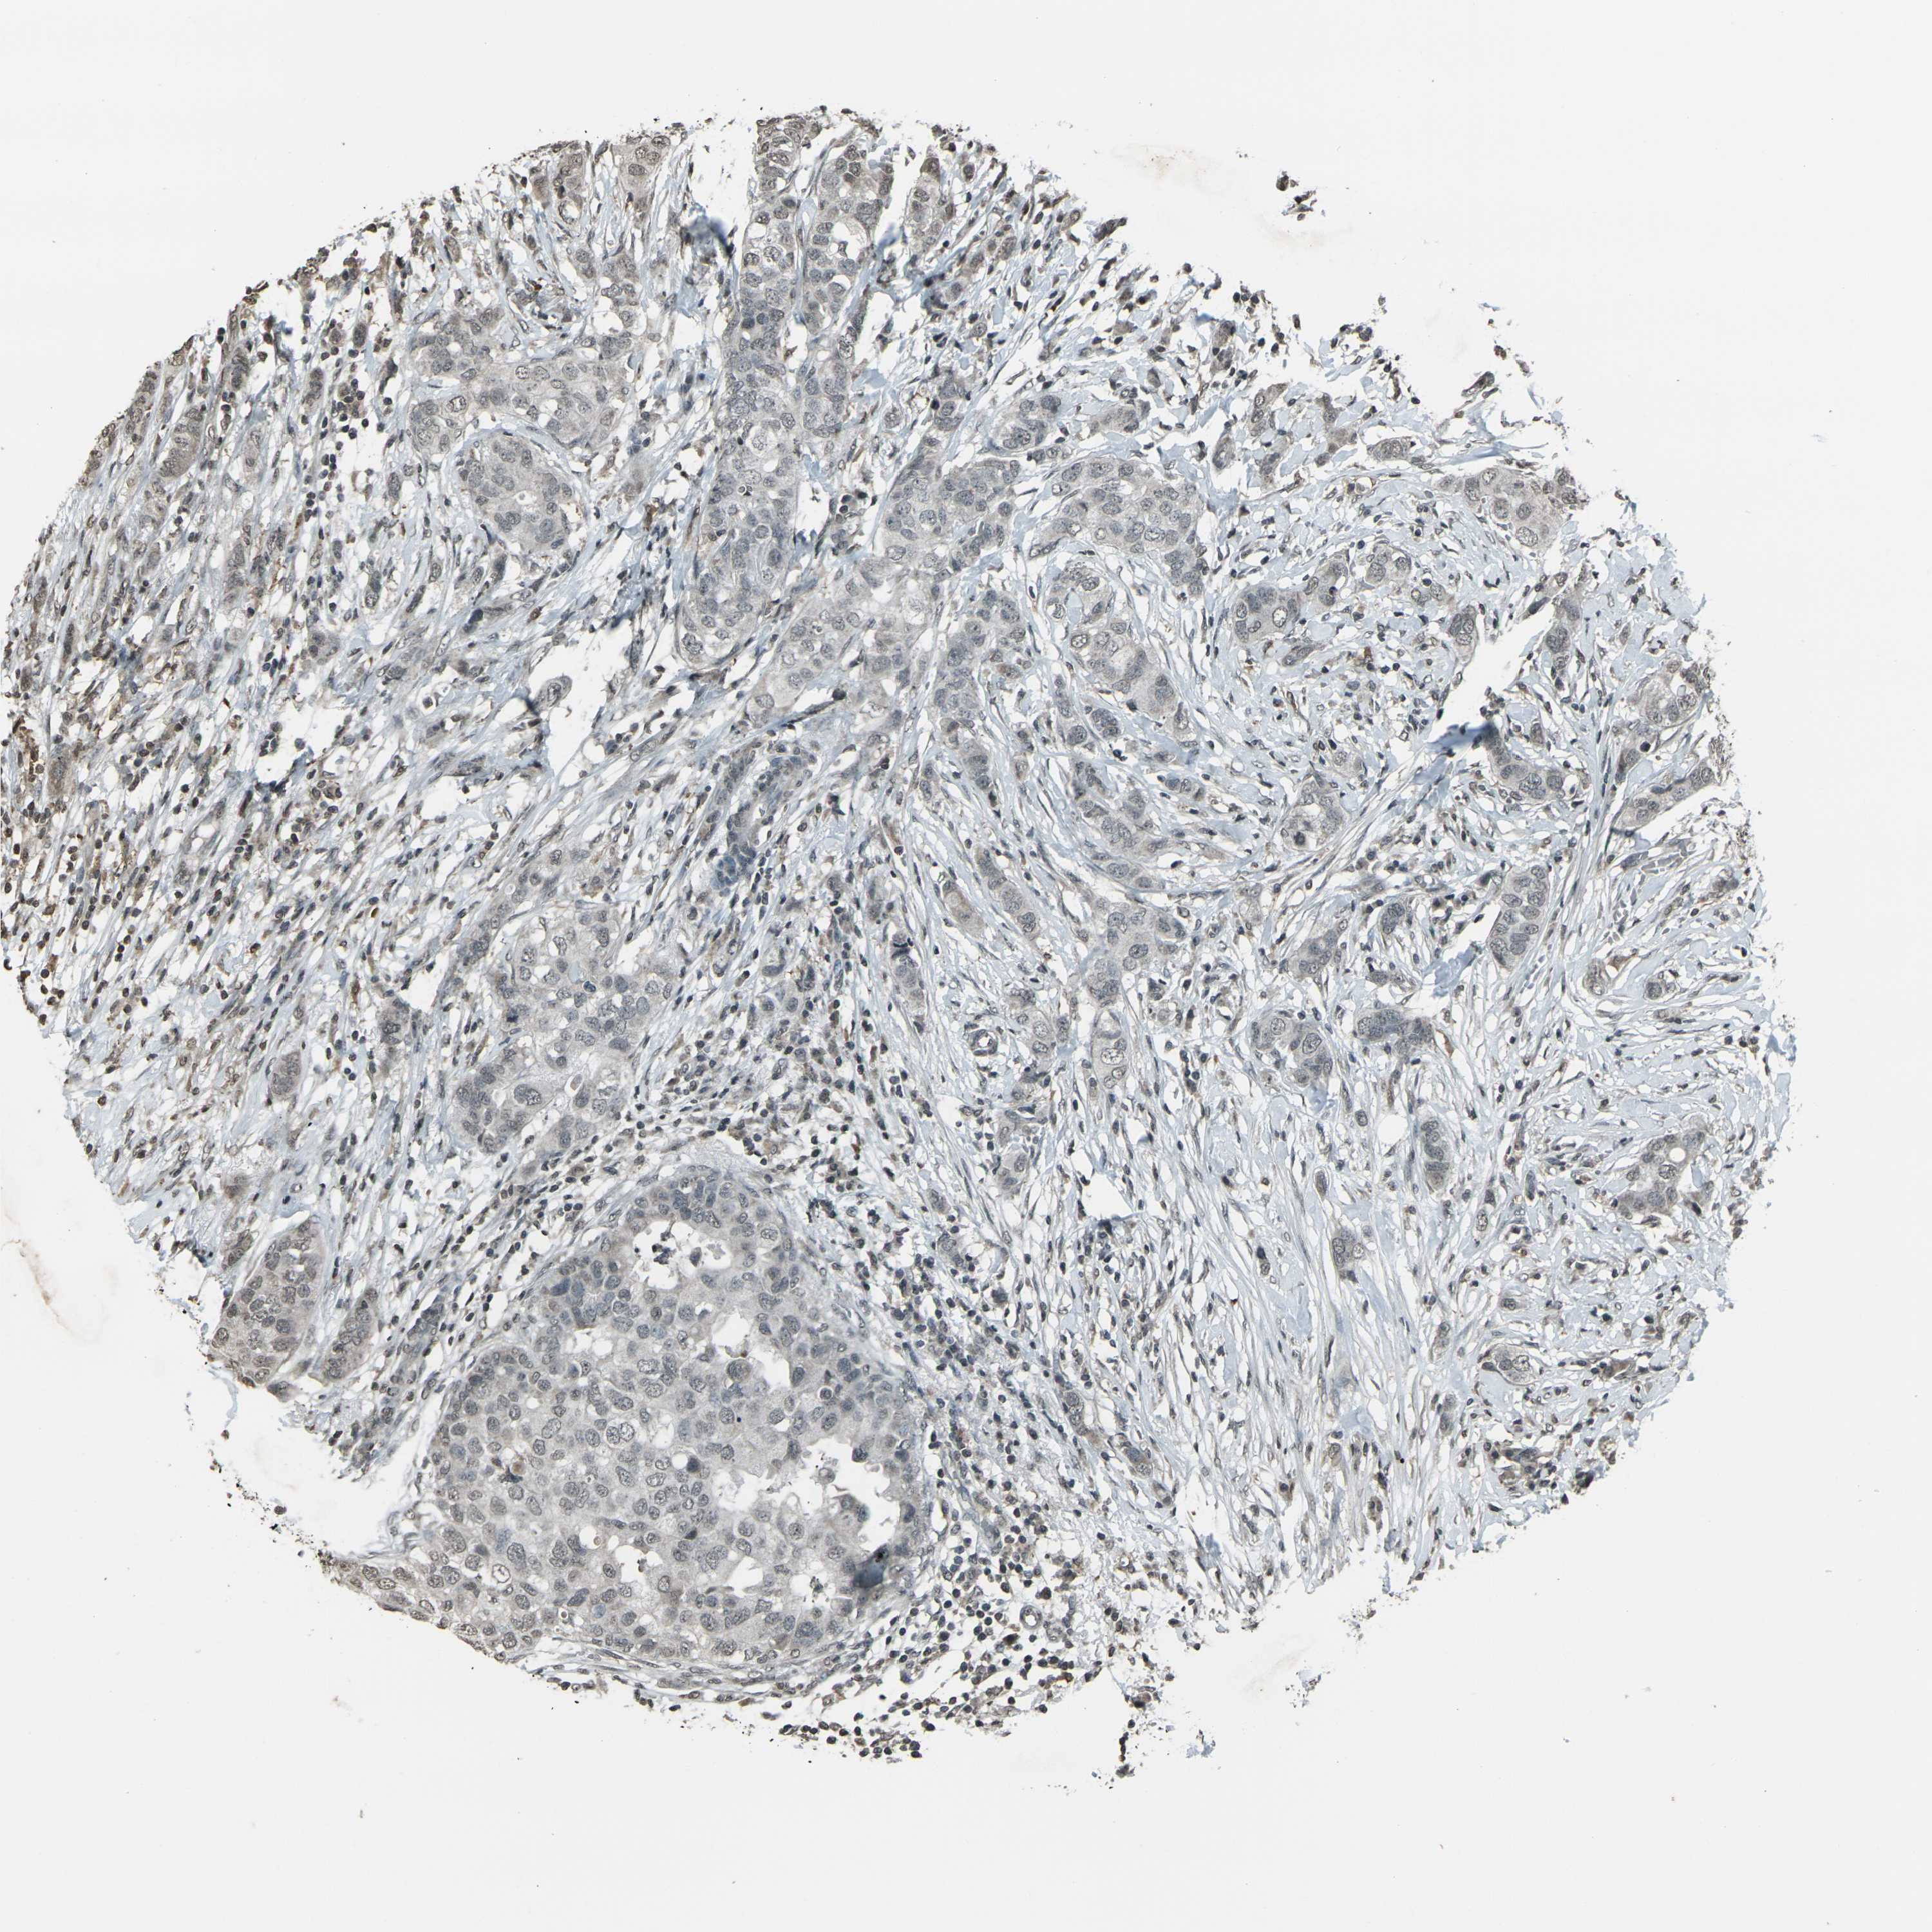

CANCER BREAST CANCER Show tissue menu

BRCA TCGA BRCA VALIDATION PROTEIN EXPRESSION